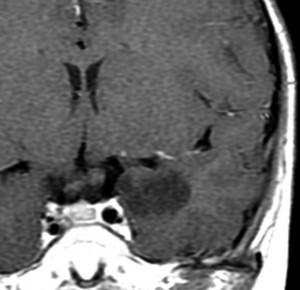

若い成人です,認知機能障害で発症しました。この画像を見るからに悪性神経膠腫,少なくともグレード3のグリオーマであることは明白です。しかし,グレード4膠芽腫あるいはグレード3退形成性星細胞腫にしては腫瘍周辺浮腫が軽すぎます。ですから,グレード3の退形成性乏突起膠腫 AO かも。認知機能の回復と温存を考量して,脳梁損傷と前交連損傷を避けて,右上前頭回と帯状回腫瘍を摘出しました。

左は術後のT1強調ガドリニウム増強像で,残存腫瘍がわかります。この腫瘍に対してICE (IFO/CDDP/VP-16) 化学療法を1コースしました。右側のMRIが1ヶ月後の画像です。このように1p/19q欠失のある退形成性乏突起膠腫は,化学療法感受性がとても高い悪性グリオーマです。ですから,手術で後遺症を残さないように,勢い込んで腫瘍を摘出しようとしないことが大切です。光顕診断はAOで,後々の解析で1p/19q codeletion でした。